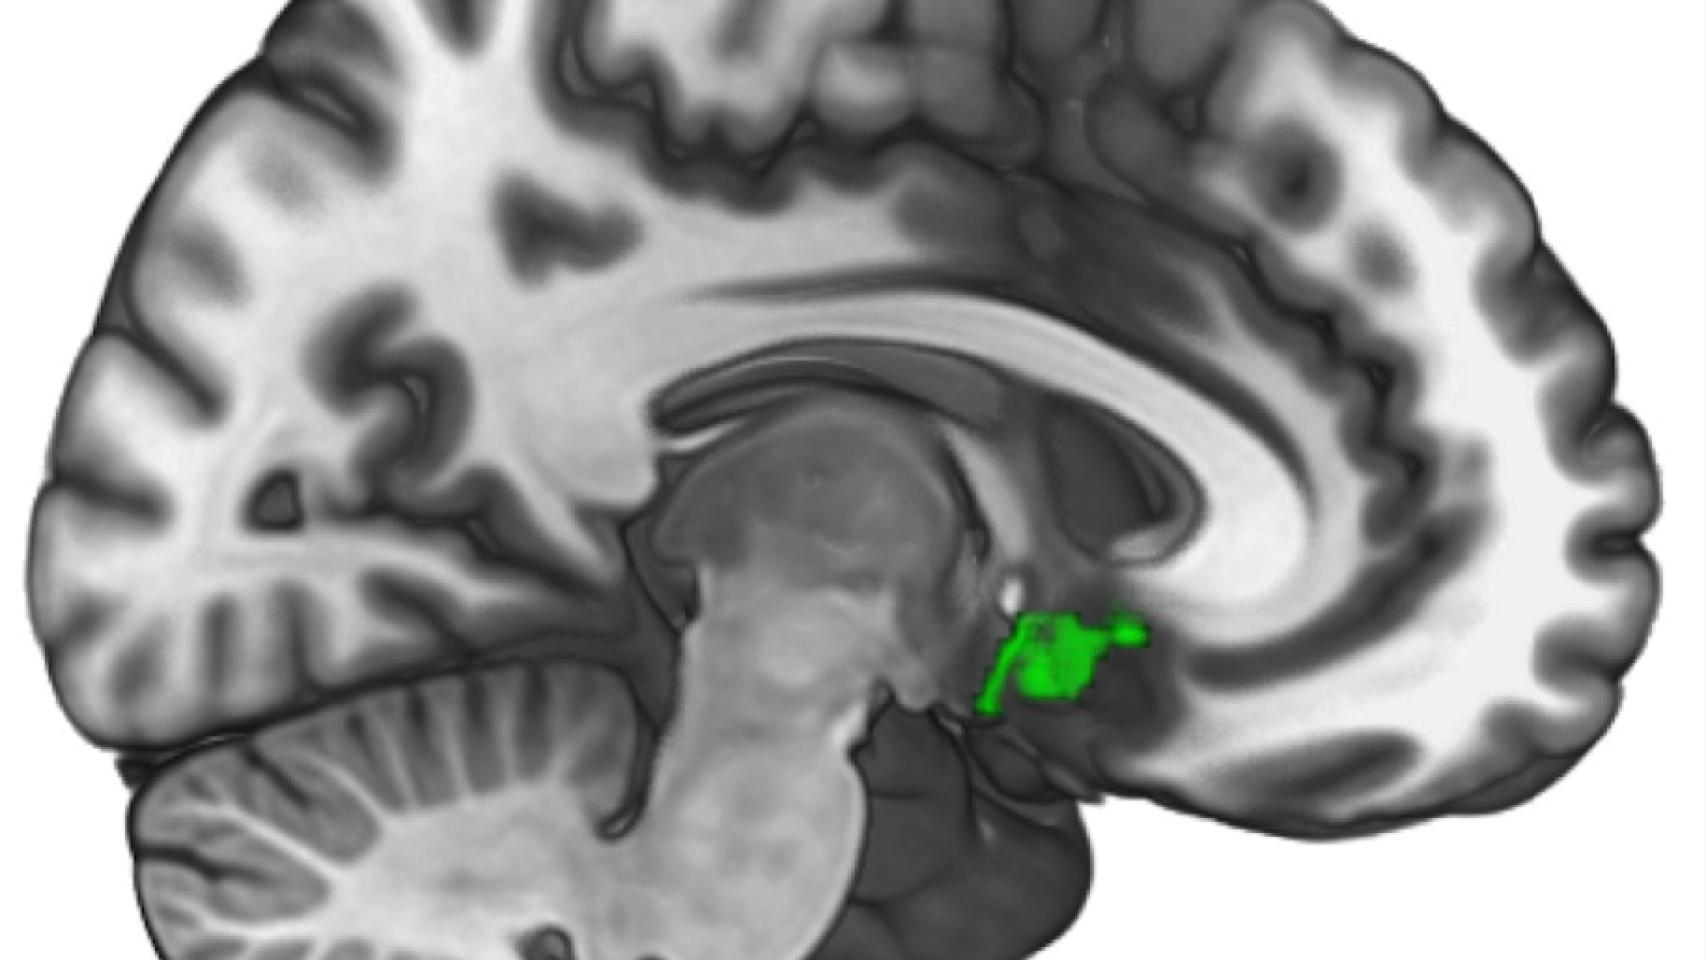

Ya sabemos qué parte del cerebro nos puede ayudar a ser mejores personas. Investigadores de la Universidad de Oxford y de la UCL, dirigidos por la psicóloga Patricia Lockwood, han hallado que una parte del cerebro muy concreta en la circunvolución del cíngulo o corteza cingular que se ilumina cuando aprendemos a hacer el bien a otras personas, con mayor o menos intensidad según seamos más o menos empáticos, según un estudio publicado en PNAS.

Así, los científicos comprobaron que ese área particular del cerebro es "la única que se activa" en el aprendizaje de decisiones que benefician a otras personas, afirma Lockwood. "La corteza cingular anterior es una región profunda del cerebro, y ya se sabía con anterioridad que su actividad está relacionada en conductas pro-sociales y morales, así como en el aprendizaje sobre las recompensas", apunta esta experta a este diario. "Sin embargo, esta región no es igualmente sensible en todo el mundo", añade. Según las pruebas realizadas, los que se calificaron a sí mismos como más empáticos mostraban más actividad en esa región cerebral cuando estaban aprendiendo a ayudar a otra persona.